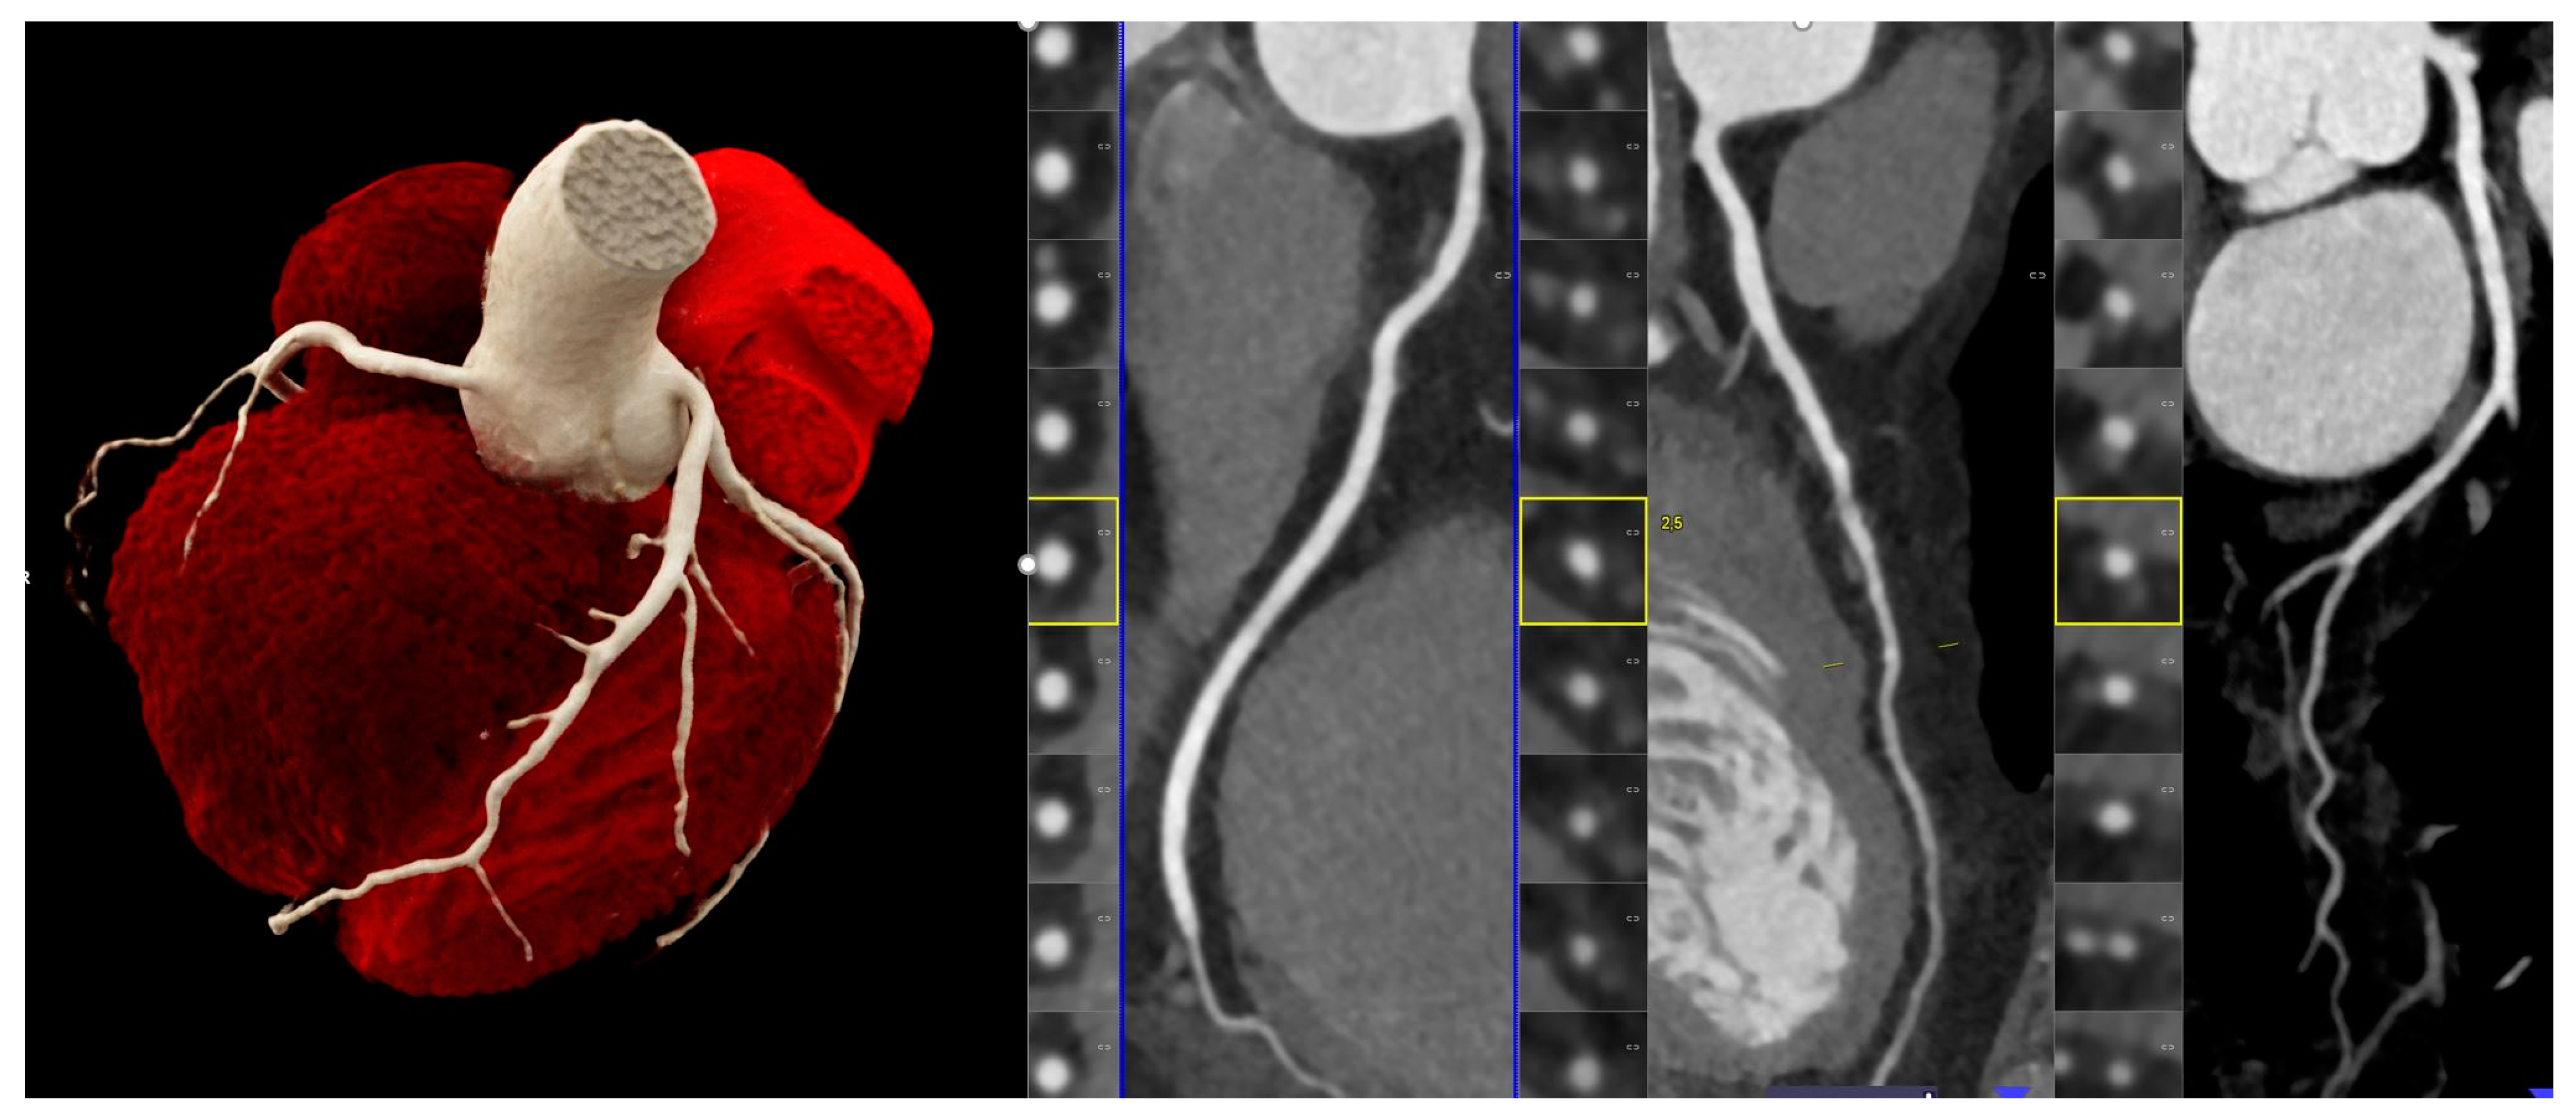

3.4. Are There Further Clinical Applications of Spectral Imaging?

3.5. Can the Ultra-High Resolution (UHR) Mode Be Implemented in Clinical Practice?